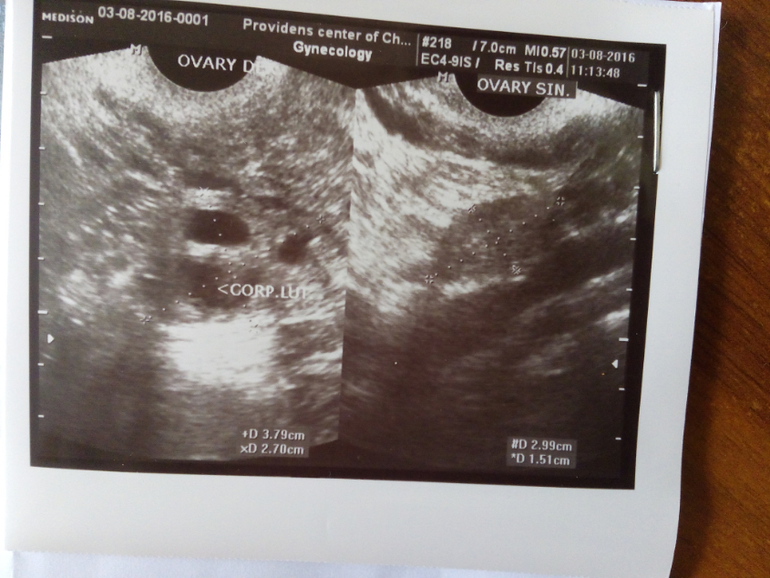

Базальная температура, ТТ, графики БТВ этом цикле О отслеживала тестами ,графиком БТ,и УЗИ.Овуляция была ранняя на 13 дц(как сказал врач на узи),и тесты среагировали в эти дни.НО! БТ не хочет подниматься,я в шоке!!!К врачу своему идти не хочу,она,мягко говоря ...,короче ничего не знает.Что делать???Я переживаю ещё вот по какому поводу:жидкости в позамоточном пространстве не было,может это не ЖТ,а киста какая нибудь,и из-за этого БТ не растёт?

Узи и график выкладываю,кто понимает,может подскажите?

Как здорово!!!Вот бы и мне так))Ну мне доктор узист сказал,что по данным УЗИ ,то у меня все шансы на Б.